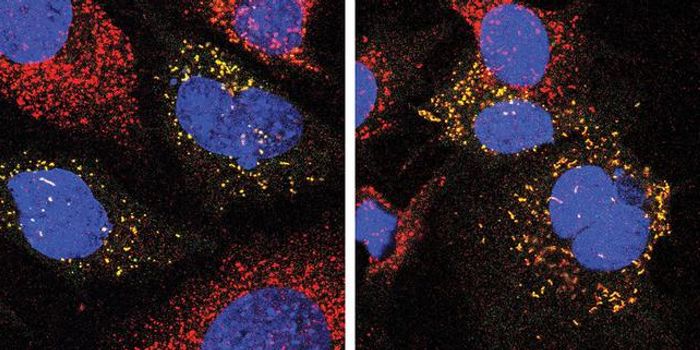

SEP 10, 2024Health & MedicineA study published in ACS Pharmacology & Translational Science indicated that long-term THC treatment can initially e ...